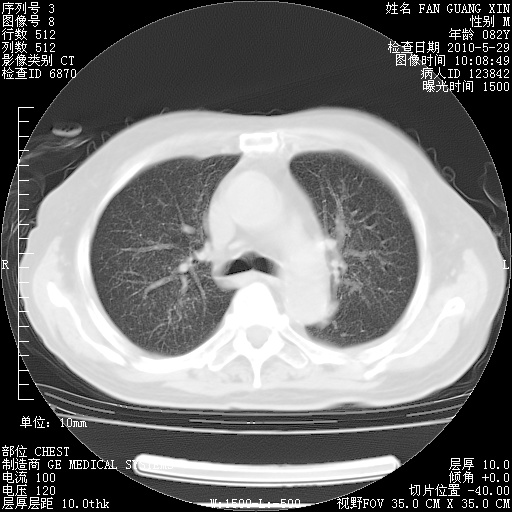

再治疗10天后的肺部CT

再治疗10天后的肺部CT 纵膈窗

肺部体征:呼吸25次/分,心率100次/分,呼吸音增粗。无干湿罗音。

血常规:15.36×10 [sup]9[/sup]/L  N0.92  L0.036  M0.045 ESR 27mm/h。

血生化:白蛋白33.30g/L  球蛋白23.67g/L  CRP 32.82mg/L 肝肾功能正常。电解质正常。

从白细胞总数和中性比例看好像合并感染。肺部纹理好像比上次多,支气管炎?其他感染?

阅读此次胸部CT,肺间质渗出性改变较入院时有吸收。目前从体温、白细胞、中性分叶明显增高,肯定存在细菌感染(发生医院感染哦,若无消化道及泌尿系统等感染的依据,肺部感染可能大)。若你院头孢哌酮舒巴坦钠耐药率较高,同意你的方案,若48小时体温仍高,可考虑使用碳青霉稀类抗菌药物,同时可予超声雾化、注意滴数时加大液体量。白蛋白33.30g/L较低哦,需加强营养等支持治疗。